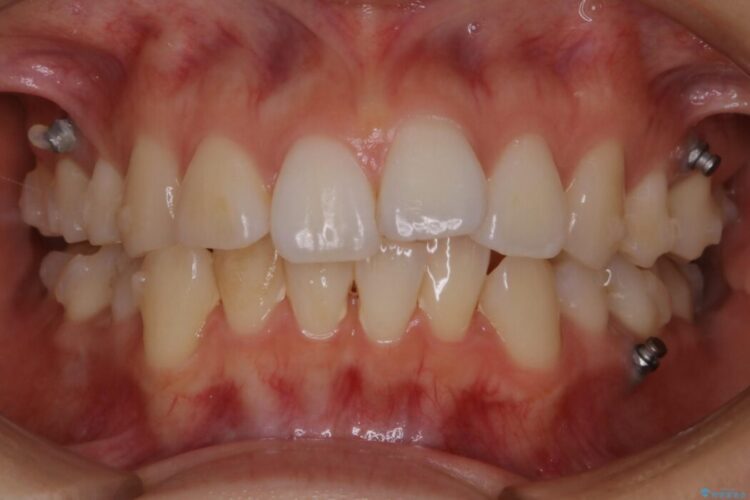

治療後について

後戻りしていた歯列もきれいに整い患者様にはご満足いただけました。

- 治療期間:1年6ヶ月

- 矯正装置:インビザライン コンプリヘンシブパッケージ

- 概算治療費:96.8万円(マイクロインプラント費用込)